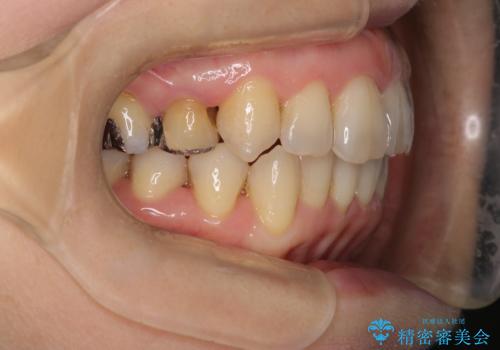

今回の治療では、右上5番の抜歯スペースを活用して八重歯(3番)を後方へ誘導しました。

インビザライン独自の3Dシミュレーションに基づき、必要な歯だけをピンポイントで動かすことで、抜歯を伴う大きな移動も効率的に行いました。

治療の結果、突出していた八重歯はきれいなアーチに収まり、左右対称でバランスの取れた口元になりました。インビザラインは自由に取り外しができるため、治療期間中も口腔内を清潔に保ちやすく、患者様もストレスなく治療を完了されました。